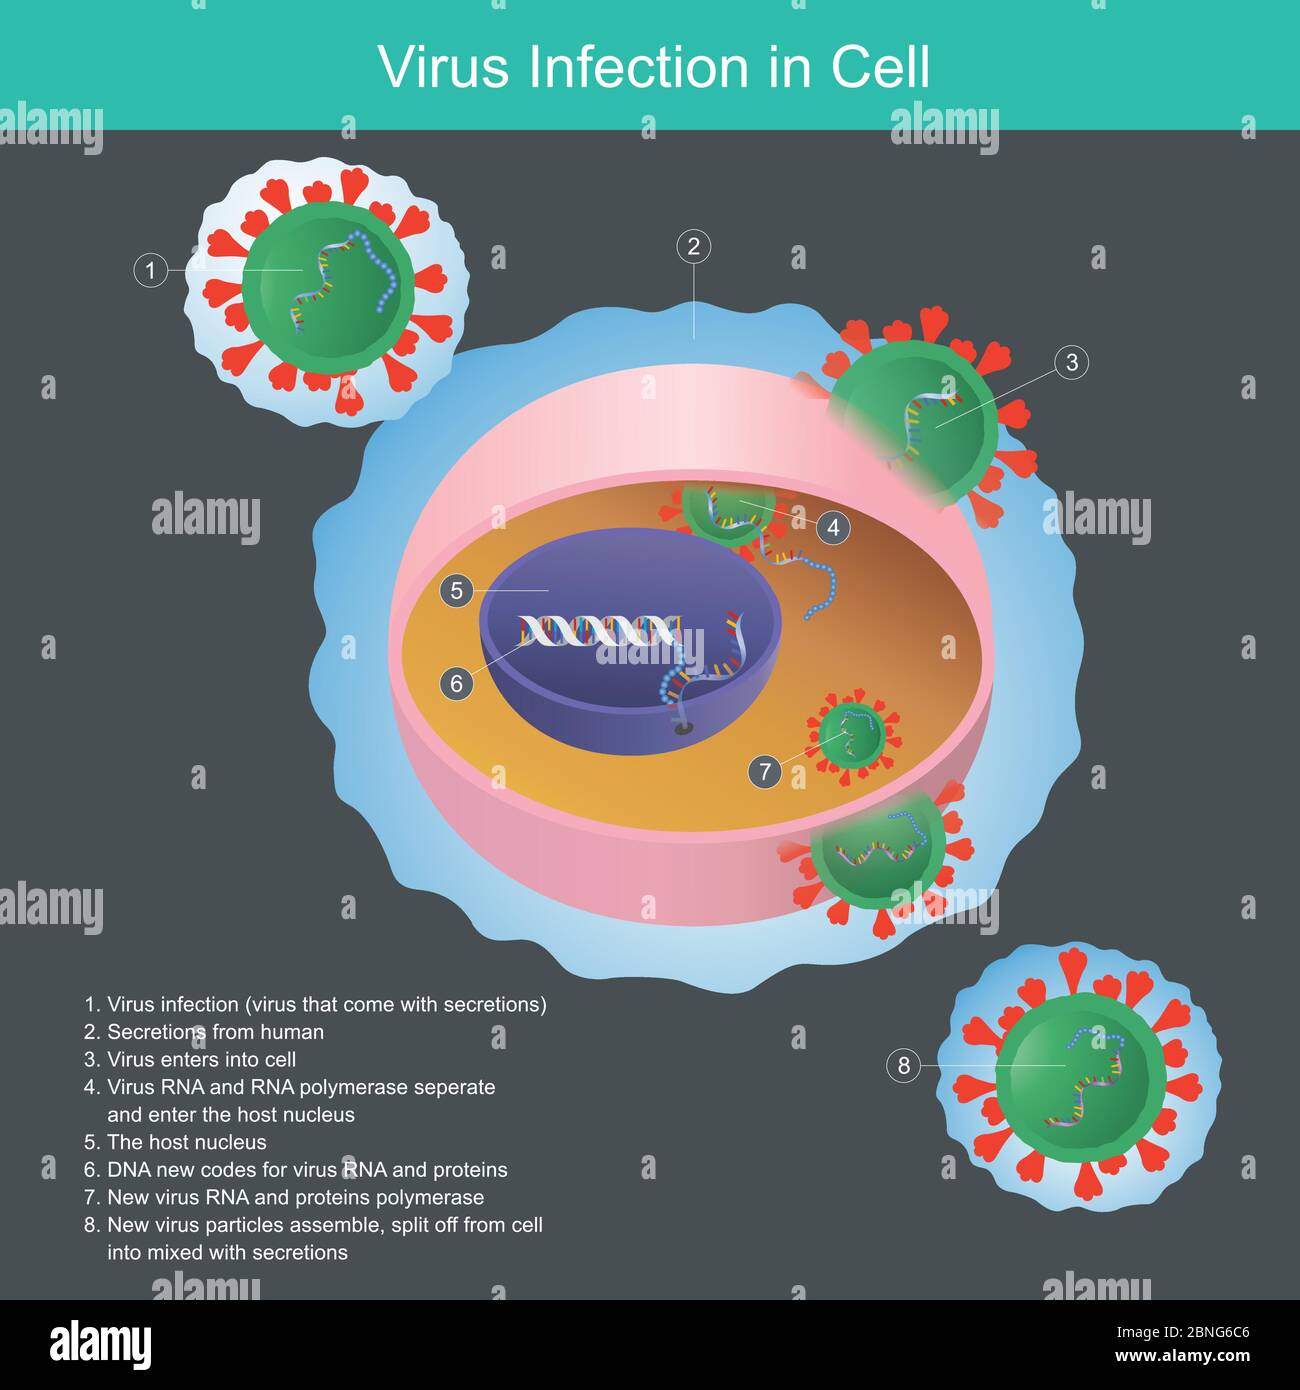

Infezione da virus in cellule. Illustrazione spiegare il virus da secrezioni umane l'infezione entra in cellule e nel nucleo. Illustrazione Vettorialehttps://www.alamy.it/image-license-details/?v=1https://www.alamy.it/infezione-da-virus-in-cellule-illustrazione-spiegare-il-virus-da-secrezioni-umane-l-infezione-entra-in-cellule-e-nel-nucleo-image357471414.html

Infezione da virus in cellule. Illustrazione spiegare il virus da secrezioni umane l'infezione entra in cellule e nel nucleo. Illustrazione Vettorialehttps://www.alamy.it/image-license-details/?v=1https://www.alamy.it/infezione-da-virus-in-cellule-illustrazione-spiegare-il-virus-da-secrezioni-umane-l-infezione-entra-in-cellule-e-nel-nucleo-image357471414.htmlRF2BNG6C6–Infezione da virus in cellule. Illustrazione spiegare il virus da secrezioni umane l'infezione entra in cellule e nel nucleo.